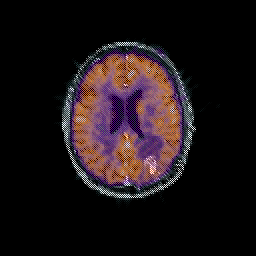

Glioma overlay -- Slice #73

[Home][Help][Clinical] Slice 73